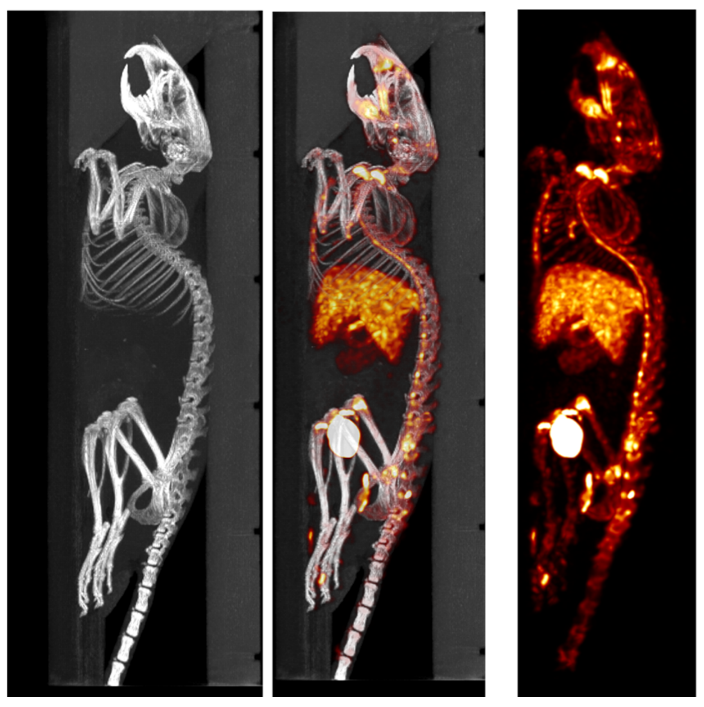

1、和PET組合的CT成像

PET/CT組合圖像:藥物代謝研究:20min動(dòng)態(tài)PET/CT圖像,藥物對(duì)肝臟有毒性,不能殘留在肝臟里,動(dòng)態(tài)成像最后肝臟不亮,說明沒有藥物殘留。Dynamic 20 minute PET acquisition, 4.44 MBq (120 μCi) @ start acquisition。

2、和SPECT組合的CT成像

SPECT/CT組合圖像,小鼠的骨骼成像:99mTc-HDP,94.35MBq (2.55mCi) @ start acquisition,采集時(shí)間60min。

和SPECT融合.png